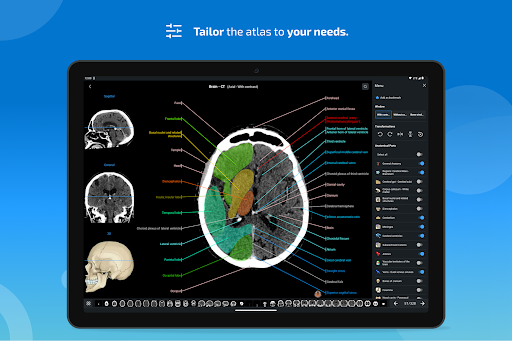

e-Anatomy tiene más de 26 000 imágenes que contienen series de imágenes en vistas axiales, coronales y sagitales, así como radiografías, angiografías, imágenes de disección, gráficos anatómicos e ilustraciones. Todas las imágenes médicas fueron etiquetadas cuidadosamente, más de 967 000 etiquetas disponibles en 12 idiomas, incluida la Terminologia Anatomica latina.

- Seleccione las etiquetas anatómicas por categoría

- Múltiples orientaciones de pantalla

- Ahora puede ocultar las estructuras una por una (nuevo botón dentro de la ventana emergente de descripción) y visualizarlas nuevamente en el menú derecho